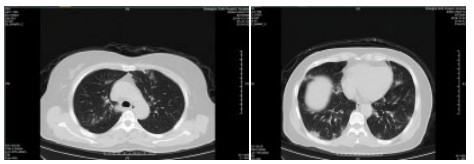

| 图 2 患者,女性,64岁,武汉籍,发病前1 d由武汉自驾车入沪,出现发热,体温39.9℃, 伴全身乏力,无咳嗽症状,无鼻塞,流涕症状,血白细胞总数及淋巴计数正常,甲乙型流感病毒筛查阴性,新型冠状病毒核酸检测阳性,肺部CT双肺多发磨玻璃结节,部分贴近胸膜,左肺有少量胸腔积液,局部小叶间隔增厚, 可见纤维条索影 Fig 2 Case 2, female, 64 years old, born in Wuhan. One day before the onset of the disease, she drove into Shanghai from Wuhan and had fever. Her body temperature was 39.9℃, with general asthenia, no cough, no nasal obstruction and running nose, normal WBC and lymphoid count, negative influenza A and B virus screening, positive novel coronavirus nucleic acid test. Lung CT showed multiple ground glass nodules, some of which were close to pleura, a small amount of pleural effusion in the left lung, and local interlobular septa was thickened, with visible fibrous streak shadow |

| 图 3 患者,女性,49岁,沪籍,发热10 d,体温最高38.5℃,伴乏力,肌肉酸痛,既往体健。否认武汉流行病学接触史,有菜场买菜史。血白细胞总数及淋巴计数正常,甲型、乙型流感筛查阴性,新型冠状病毒核酸检测阳性。肺部CT提示双肺磨玻璃结节,可见血管充血,增粗,穿行,部分贴近胸膜,伴小叶间隔增厚 Fig 3 Case 3, female, 49 years old, born in Shanghai, had fever for 10 days, body temperature 38.5℃, with fatigue, muscle pain, previous physical fitness. She denied the history of epidemic exposure of Wuhan, but had the history of shopping in market. Normal WBC and lymphoid count, negative influenza A and B virus screening, positive novel coronavirus nucleic acid test. Lung CT showed bilateral ground glass nodules with hyperemia, thickening and passage of blood vessels. Some were close to pleura with thickening of interlobular septum |